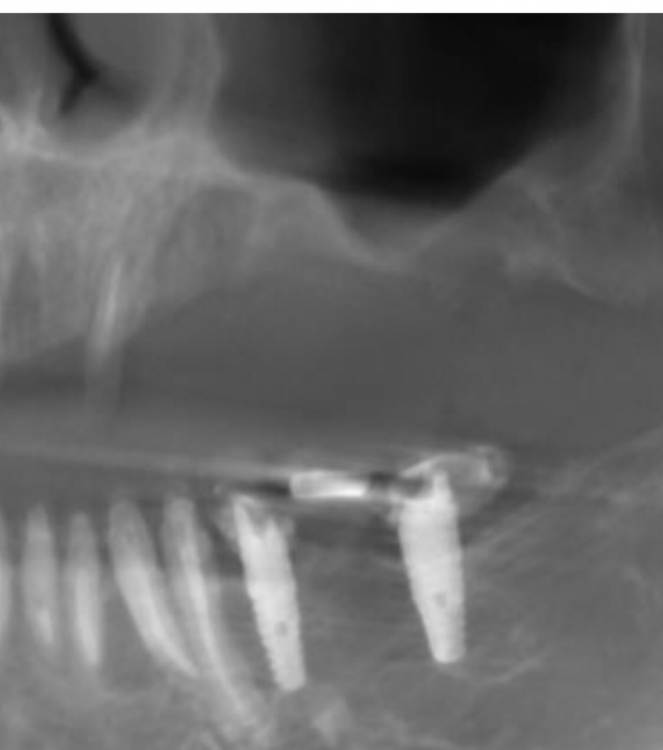

annda Опубликовано 29 апреля, 2021 Поделиться Опубликовано 29 апреля, 2021 (изменено) Интересующая область-14. Пациентка обратилась для протезирования дефектов полости рта.Было предложено удалить весь верх и низ.На верху было предложено все на 6,внизу все на 4х,но решила сделать все на 5(а вот так вот). Поступил категорический отказ удалять верхние передние зубы(на приеме подвижность 1-2й степени).Тогда как альтернатива предложен съемник на локаторах как временный вариант(с тайной мыслью-"вот поносишь и все равно придешь за первым вариантом") На операции одномоментное удаление боковых верхних и низа,установка имплантатов,формики и нагрузка в соответствии с торками.Дикий дефект в области 14 просто откюретажили до костной ткани,грануляции вырезали. Через 4 месяца приносит новую КТ.Я просто онемела.Зубы на верхней челюсти неподвижны от слова совсем...Вот что это было и есть?? Изменено 29 апреля, 2021 пользователем annda 1 Ссылка на комментарий

annda Опубликовано 29 апреля, 2021 Автор Поделиться Опубликовано 29 апреля, 2021 По протезке не было ничего, от слова совсем. Даже кривые настройки КТ не могут так исказить картину:))Срезы одни и те же , видны на обоих снимках, зубы центральные принадлежат одному человеку. Кстати, 68 лет от роду... Кость уже пощупала фрезой, абсолютно полноценная костяка... Ссылка на комментарий